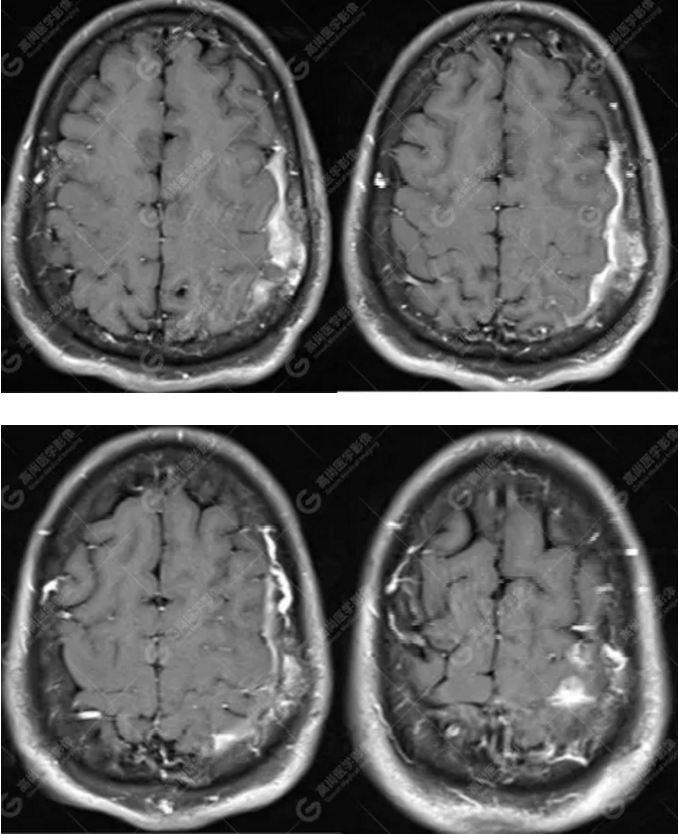

MR圖像

左側(cè)額頂部顱骨骨質(zhì)破壞并相鄰硬腦膜增厚強(qiáng)化,考慮Rosai Dorfman?。≧DD)可能,需與朗格漢斯細(xì)胞組織細(xì)胞增生癥鑒別。

典型的RDD在MRI上T1WI 呈等信號(hào),T2WI及 DWI為等-低信號(hào),增強(qiáng)掃描多為明顯均勻強(qiáng)化,多伴有腦膜尾征,部分病例伴有不同程度的腦水腫。T2WI 像 RDD 病灶中出現(xiàn)聚集的低信號(hào)影及 CT檢查沒有鈣化是 RDD 的特征性影像學(xué)表現(xiàn)。